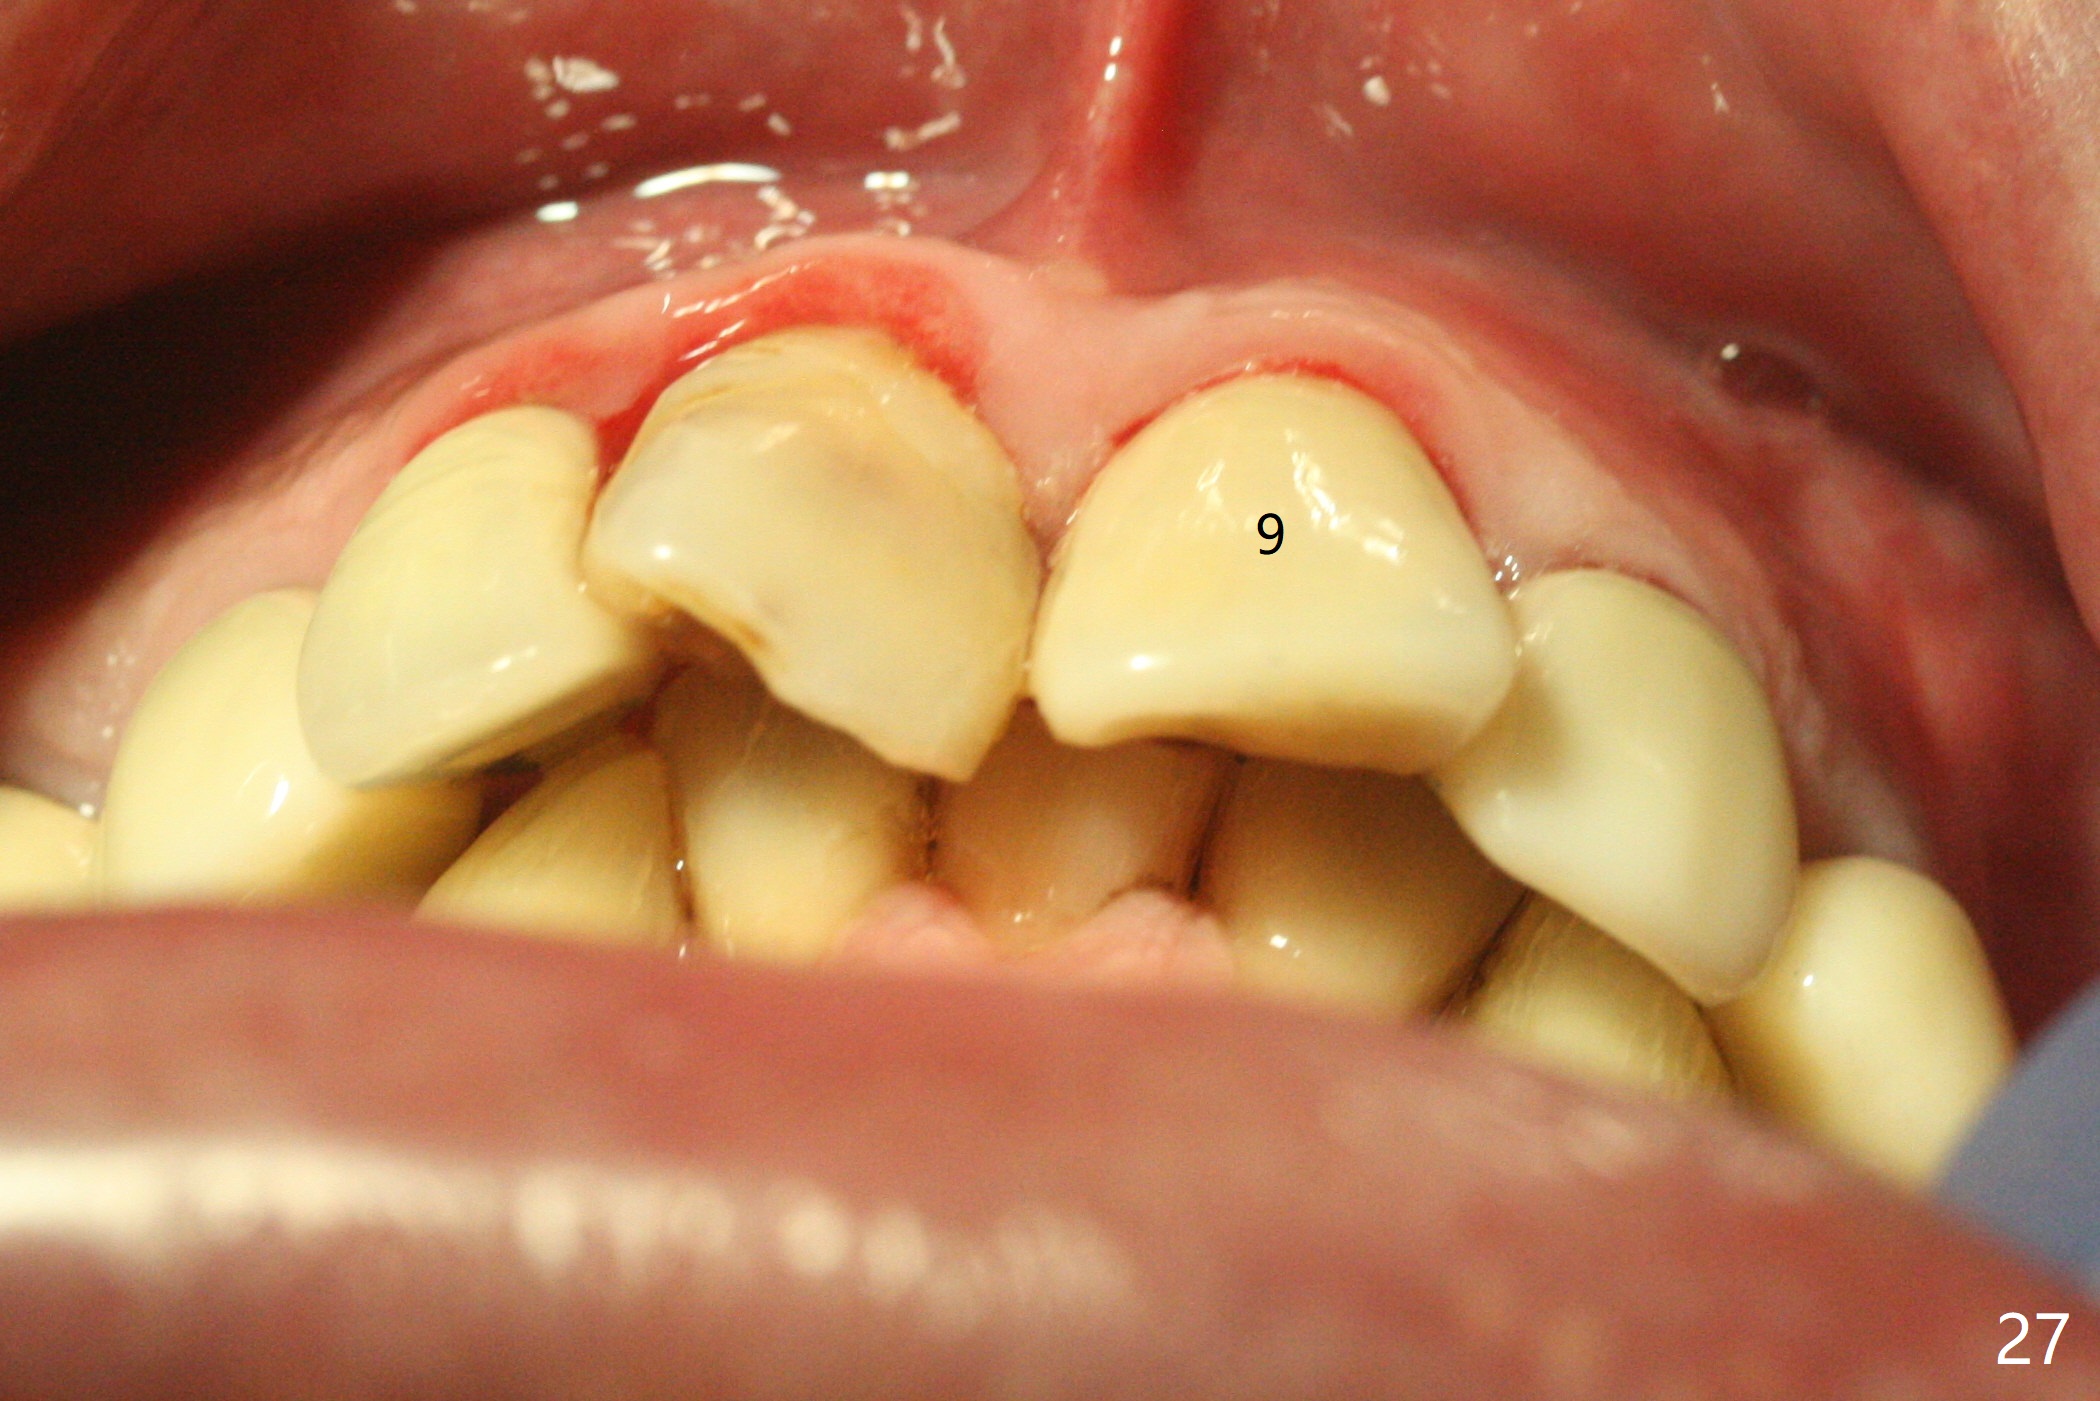

Six months post cementation, the tooth #9 becomes symptomatic. Is it possible that the implant at #10 is too close to the root of #9? It is asymptomatic after pulpotomy, but the tooth fractures equi/supragingivally. Two PAs taken while RCT show osteointegration at #10-12 (Fig.18,19). While the bone density increases at #10 regular implant, there is minimal bone loss around the 1-piece implants 13 months post cementation (18 months postop, Fig.20,21). The gingiva remains healthy 19 months post cementation (Fig.22). 76岁病人突然打电话说一个植牙牙冠松动,其实9号牙(自然牙)折裂,6,10-13号牙植牙好像没有骨质吸收(图二十三至二十五),10-13牙位牙龈健康(图二十六,行使功能五年)。9号牙牙冠重新粘固后,显示前牙深覆合,深覆盖(图二十七,二十八)。如果再次脱落需要植牙,选择一段式有助于植入和修复,因为植体和基台直径小。两段式植牙相对基台直径至少4,或者4.5毫米,前牙修复显得笨重。由于9,10牙根和植体接近,9号牙植体需要偏小而长,3x14或者15毫米(图二十九)。